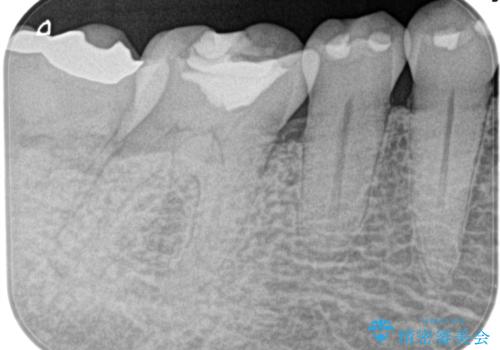

- 1週間前から冷たいもので強い持続痛を感じることを主訴に来院されました。

歯髄診断と痛みの再現により原因歯を特定し、症候性不可逆性歯髄炎の診断となりました。

根管治療〜オールセラミッククラウン(エクセレント)の治療を行なっております。

根管治療後の最終補綴物は予後に大きく関わります。